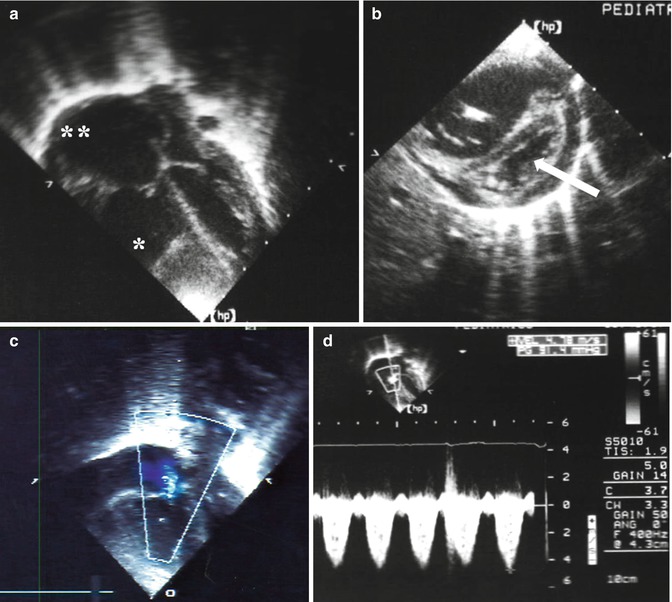

Echocardiographic signs in a case of pulmonary hypertension: (a) severe enlargement of the right ventricle (asterisk) and atrium (double asterisk); (b) hypertrophy of the right ventricle with shift of the ventricular septum (arrow) toward the left ventricle; (c) blood regurgitation through the tricuspid valve; (d) pulmonary hypertension: the overall value is about 100 mmHg resulting from the gradient through the tricuspid valve (91.4 mmHg) plus the atrial pressure (10 mmHg)